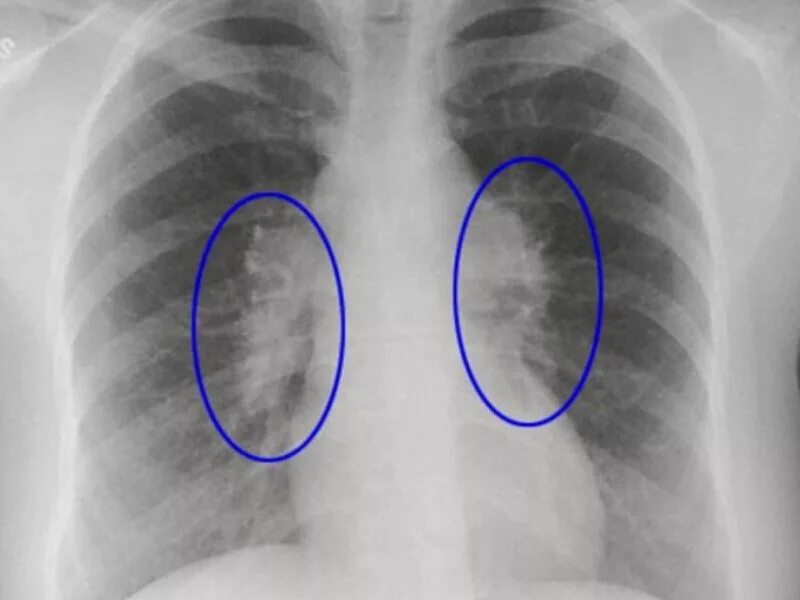

Фиброзное изменение левого легкого